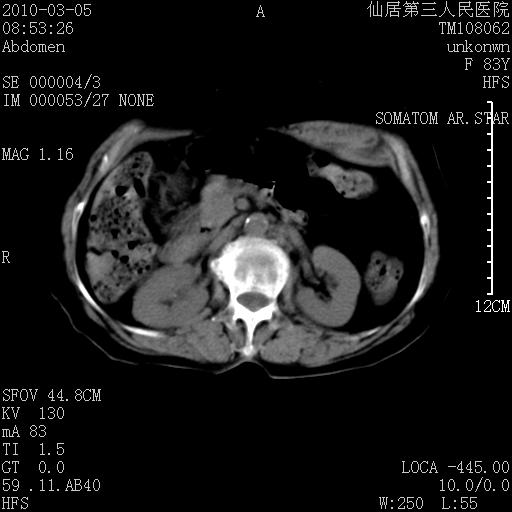

标题: CT24879:腹直肌病变。在线等。

女性,83y,腹痛一周。

考虑左侧腹直肌血肿,肿瘤性病变待排。

增强看看,mfh可能性大,次之可考虑血肿、bfh、转移瘤、神经纤维瘤、侵袭性韧带样纤维瘤等。肝内钙化灶,右肾结石。